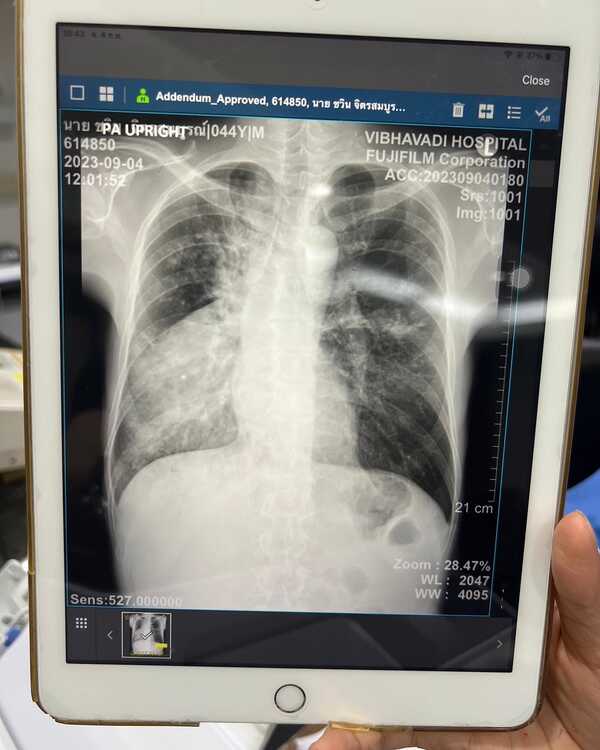

ทำเอาแฟนคลับตกอกตกใจและเป็นห่วงกันมาก ๆ เมื่อล่าสุด (5 กันยายน 2566) นักร้องชื่อดัง จั๊ก ชวิน ได้โพสต์ภาพตัวเองกำลังรักษาตัวอยู่ที่โรงพยาบาล พร้อมภาพผลเอกซเรย์ปอด พร้อมกับเปิดเผยว่า ตนเองกำลังป่วยด้วยโรควัณโรค

สรุปคือวัณโรครับประทานปอด ยังดีที่รู้เร็ว ก็รักษากันไป น่าจะได้นอนอยู่โรงบาลหลายวันแคนเซิลงานไปแล้วบางส่วน ส่วนเพื่อนเพื่อนพี่น้องที่จะมาเยี่ยมกรุณาใส่หน้ากาก N95 เท่านั้นนะครับ #จั๊กชวิน #ระนะจั๊ก_รักนะจ๊ะ"